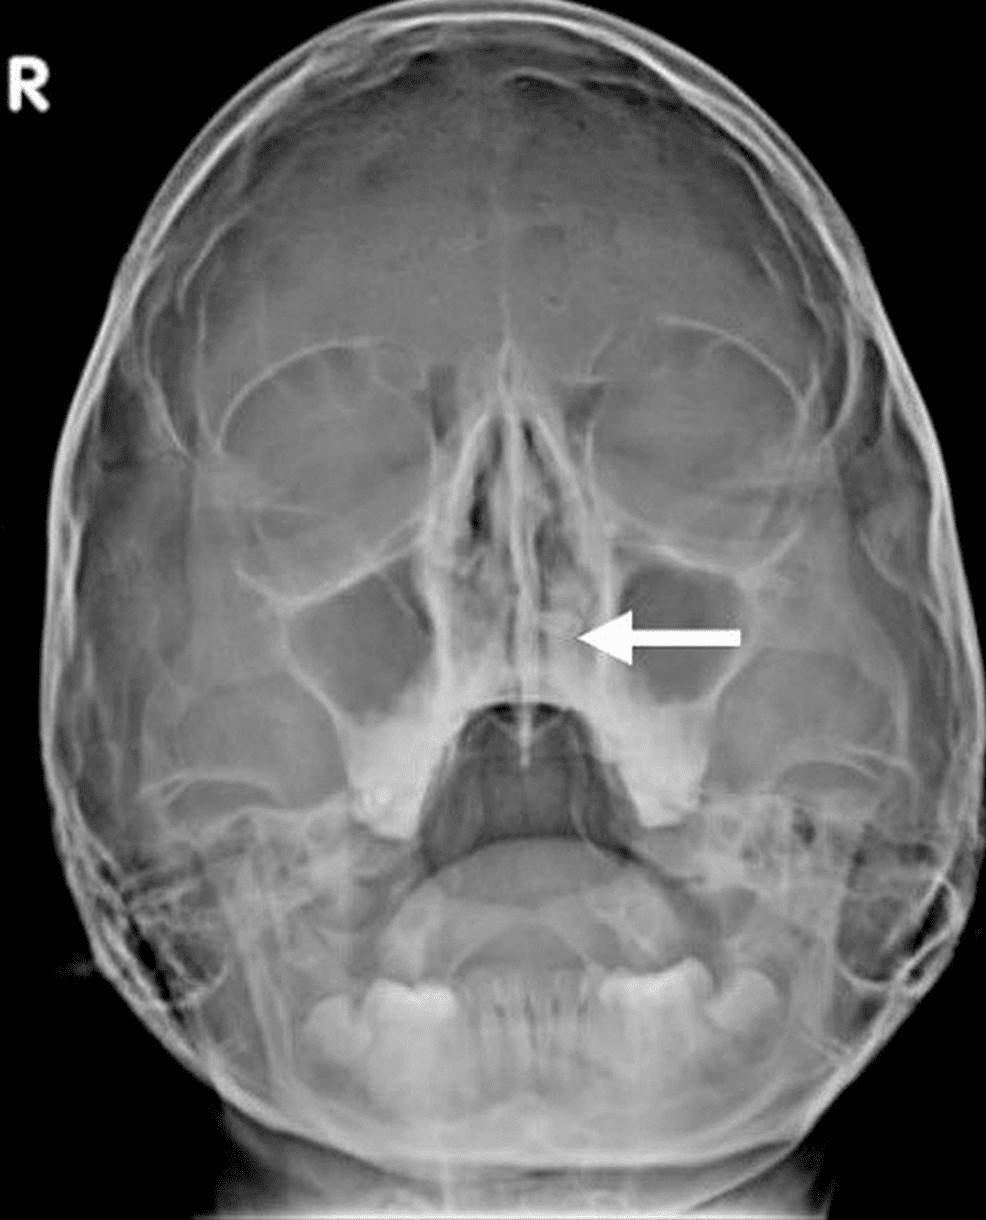

Raro de diente ectópico intranasal en mujer joven se registra en la literatura  Imagen coronal que muestra una estructura similar a un hueso (flecha blanca) incrustada en el paladar duro que se extiende hacia la cavidad nasal izquierda. Raro de diente ectópico intranasal en mujer joven se registra en la literatura  Tomografía computarizada axial que muestra un diente ectópico en la cavidad nasal izquierda rodeado de tejido blando (flecha blanca). Raro de diente ectópico intranasal en mujer joven se registra en la literatura  La radiografía simple muestra la estructura radiopaca en la fosa nasal izquierda, incrustada en el paladar duro (flecha blanca). Raro de diente ectópico intranasal en mujer joven se registra en la literatura  Imagen sagital que muestra la extensión completa de un diente intranasal (flecha blanca), que se encuentra incrustado en el paladar duro.

Recalcaron además la importancia de las imágenes radiológicas que ayudaron en el diagnóstico de un diente ectópico.